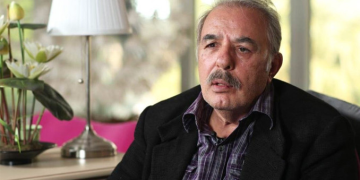

Eskişehir’de KOAH hastalığı nedeniyle yaşadığı nefes darlığından ötürü aldığı ‘Solunum Rehabilitasyonu’ ile kurtulan 66 yaşındaki İsmail Geçer, “Nefes almayı bu yaşıma kadar hakikat düzgün bilmiyormuşum” dedi.

Muayene olduğu göğüs hastalıkları profesörünün teneffüs rehabilitasyonu tavsiye etmesiyle gelerek teneffüs tedavisine başlayan İsmail Geçer’in hayatı, 20’nci seansla değişmeye başladı. Merkeze birinci geldiğinde nefes darlığından ötürü şikayetlerini bile tam olarak anlatamayan Geçer, “Nefes almayı bu yaşıma kadar hakikat düzgün bilmiyormuşum” dedi.

Yaşadığı nefes darlığı sorununun azalmasıyla hayatının değiştiğini, artık 4’üncü kattaki konutuna çıkabildiğini belirten İsmail Geçer, “15 yıldan beri ilaç kullanıyorum. 5 Mayıs’ta bir hafta hastaneye yattım. Bir hocamın tavsiyesiyle teneffüs tedavisine yönlendirildim. Fizyomer’e geldim, Türkan Hoca’ya muayene oldum. Türkan hoca bana nefes idmanı tavsiyesinde bulundu. İdmana başladım. Yaklaşık 23 günden beri geliyorum. Birinci 15 günüm Hüseyin hocayla başladı. Kendisinden Allah razı olsun, çok şad kaldım. Nefes almayı bu yaşıma kadar gerçek düzgün bilmiyormuşum. Artık çok şükür yürüyorum. 4 kat merdiveni bile çıkabiliyorum” dedi.